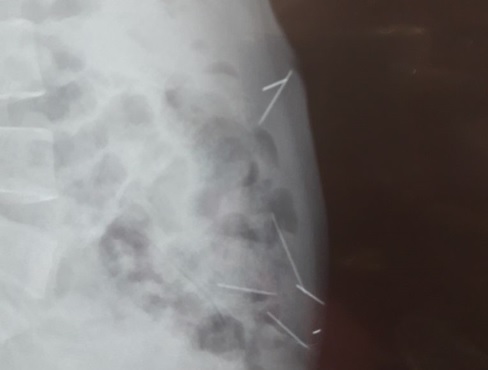

SANTO DOMINGO.-Médicos del Hospital Francisco Moscoso Puello extrajeron cinco de las siete agujas que llevaba dentro una mujer en su vientre.

María Morel de 41 años dijo desconocer cómo se introdujeron los cuerpos extraños. Noticias SIN dio la primicia este miércoles. Se espera que en las próximas horas les sean retiradas el resto de las agujas.